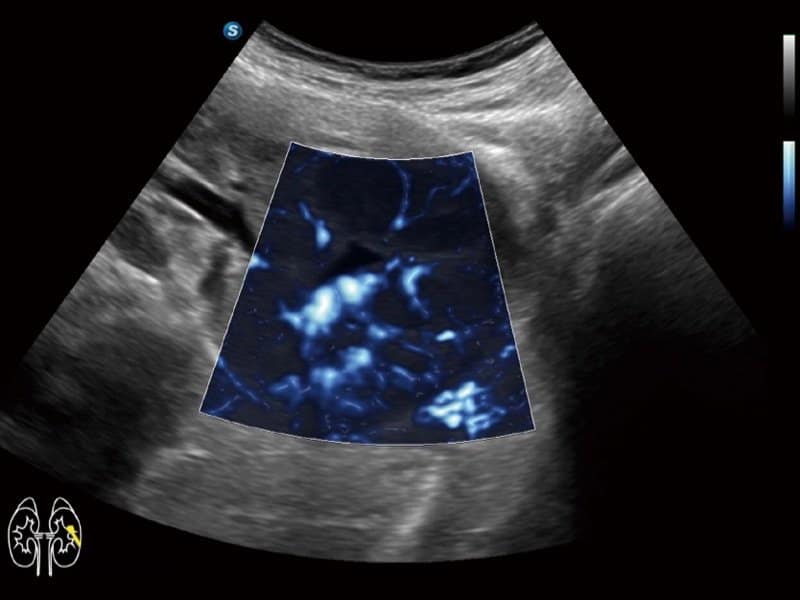

Klinische Bilder

- Radiologie: Quantitative Beurteilung der Lebersteatose durch ATI, Strain-Elastographie und kontrastverstärkter Ultraschall (CEUS)